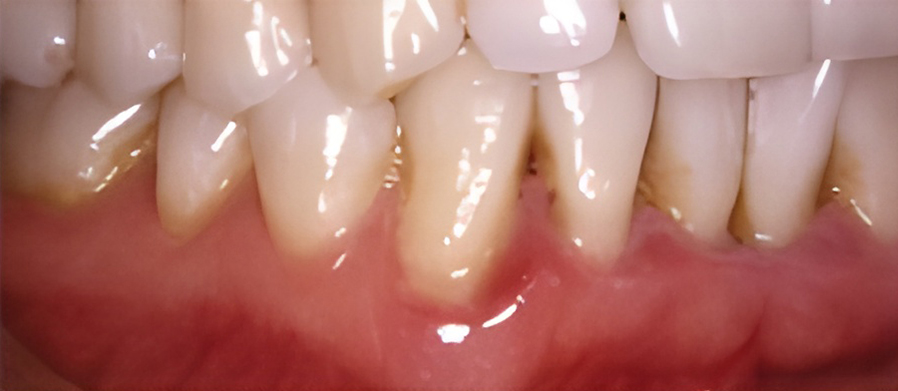

If you have signs of unhealthy gums such as redness, swelling, bleeding, tenderness, and bad breath, our doctor may recommend root planing and curettage. Root planing and curettage smooth the root surfaces beneath the gum line to remove plaque and calculus, and remove inflamed tissue so that healthy gum tissue may heal next to the cleaned and smooth tooth surface.

Because this procedure goes deeper than regular teeth cleaning, local anesthetic is needed to numb the gum.

Two office visits are usually required to complete the procedure.

The primary cause of periodontal disease is the accumulation of bacterial plaque at and under the gum line.

If plaque is not removed daily through brushing and flossing, the bacteria will cause the gum tissue to become red and swollen. At this first stage, gingivitis can and may be reversed by visiting your dentist and dental hygienist, along with your efforts at maintaining good dental hygiene.

If gingivitis is left untreated, the plaque can spread to the roots, causing an infection and damage to the supporting bone and soft tissue. The gums may separate from the tooth and start to recede. A pocket can form below the gum line and trap plaque and food. As periodontitis progresses, up to one-third of the bone can be lost.

In this later stage, half or more of the original bone holding the tooth is lost, and the pocket becomes very deep. The gums recede even more and the tooth may appear longer because the root is exposed. The tooth may eventually fall out due to a lack of supporting bone.